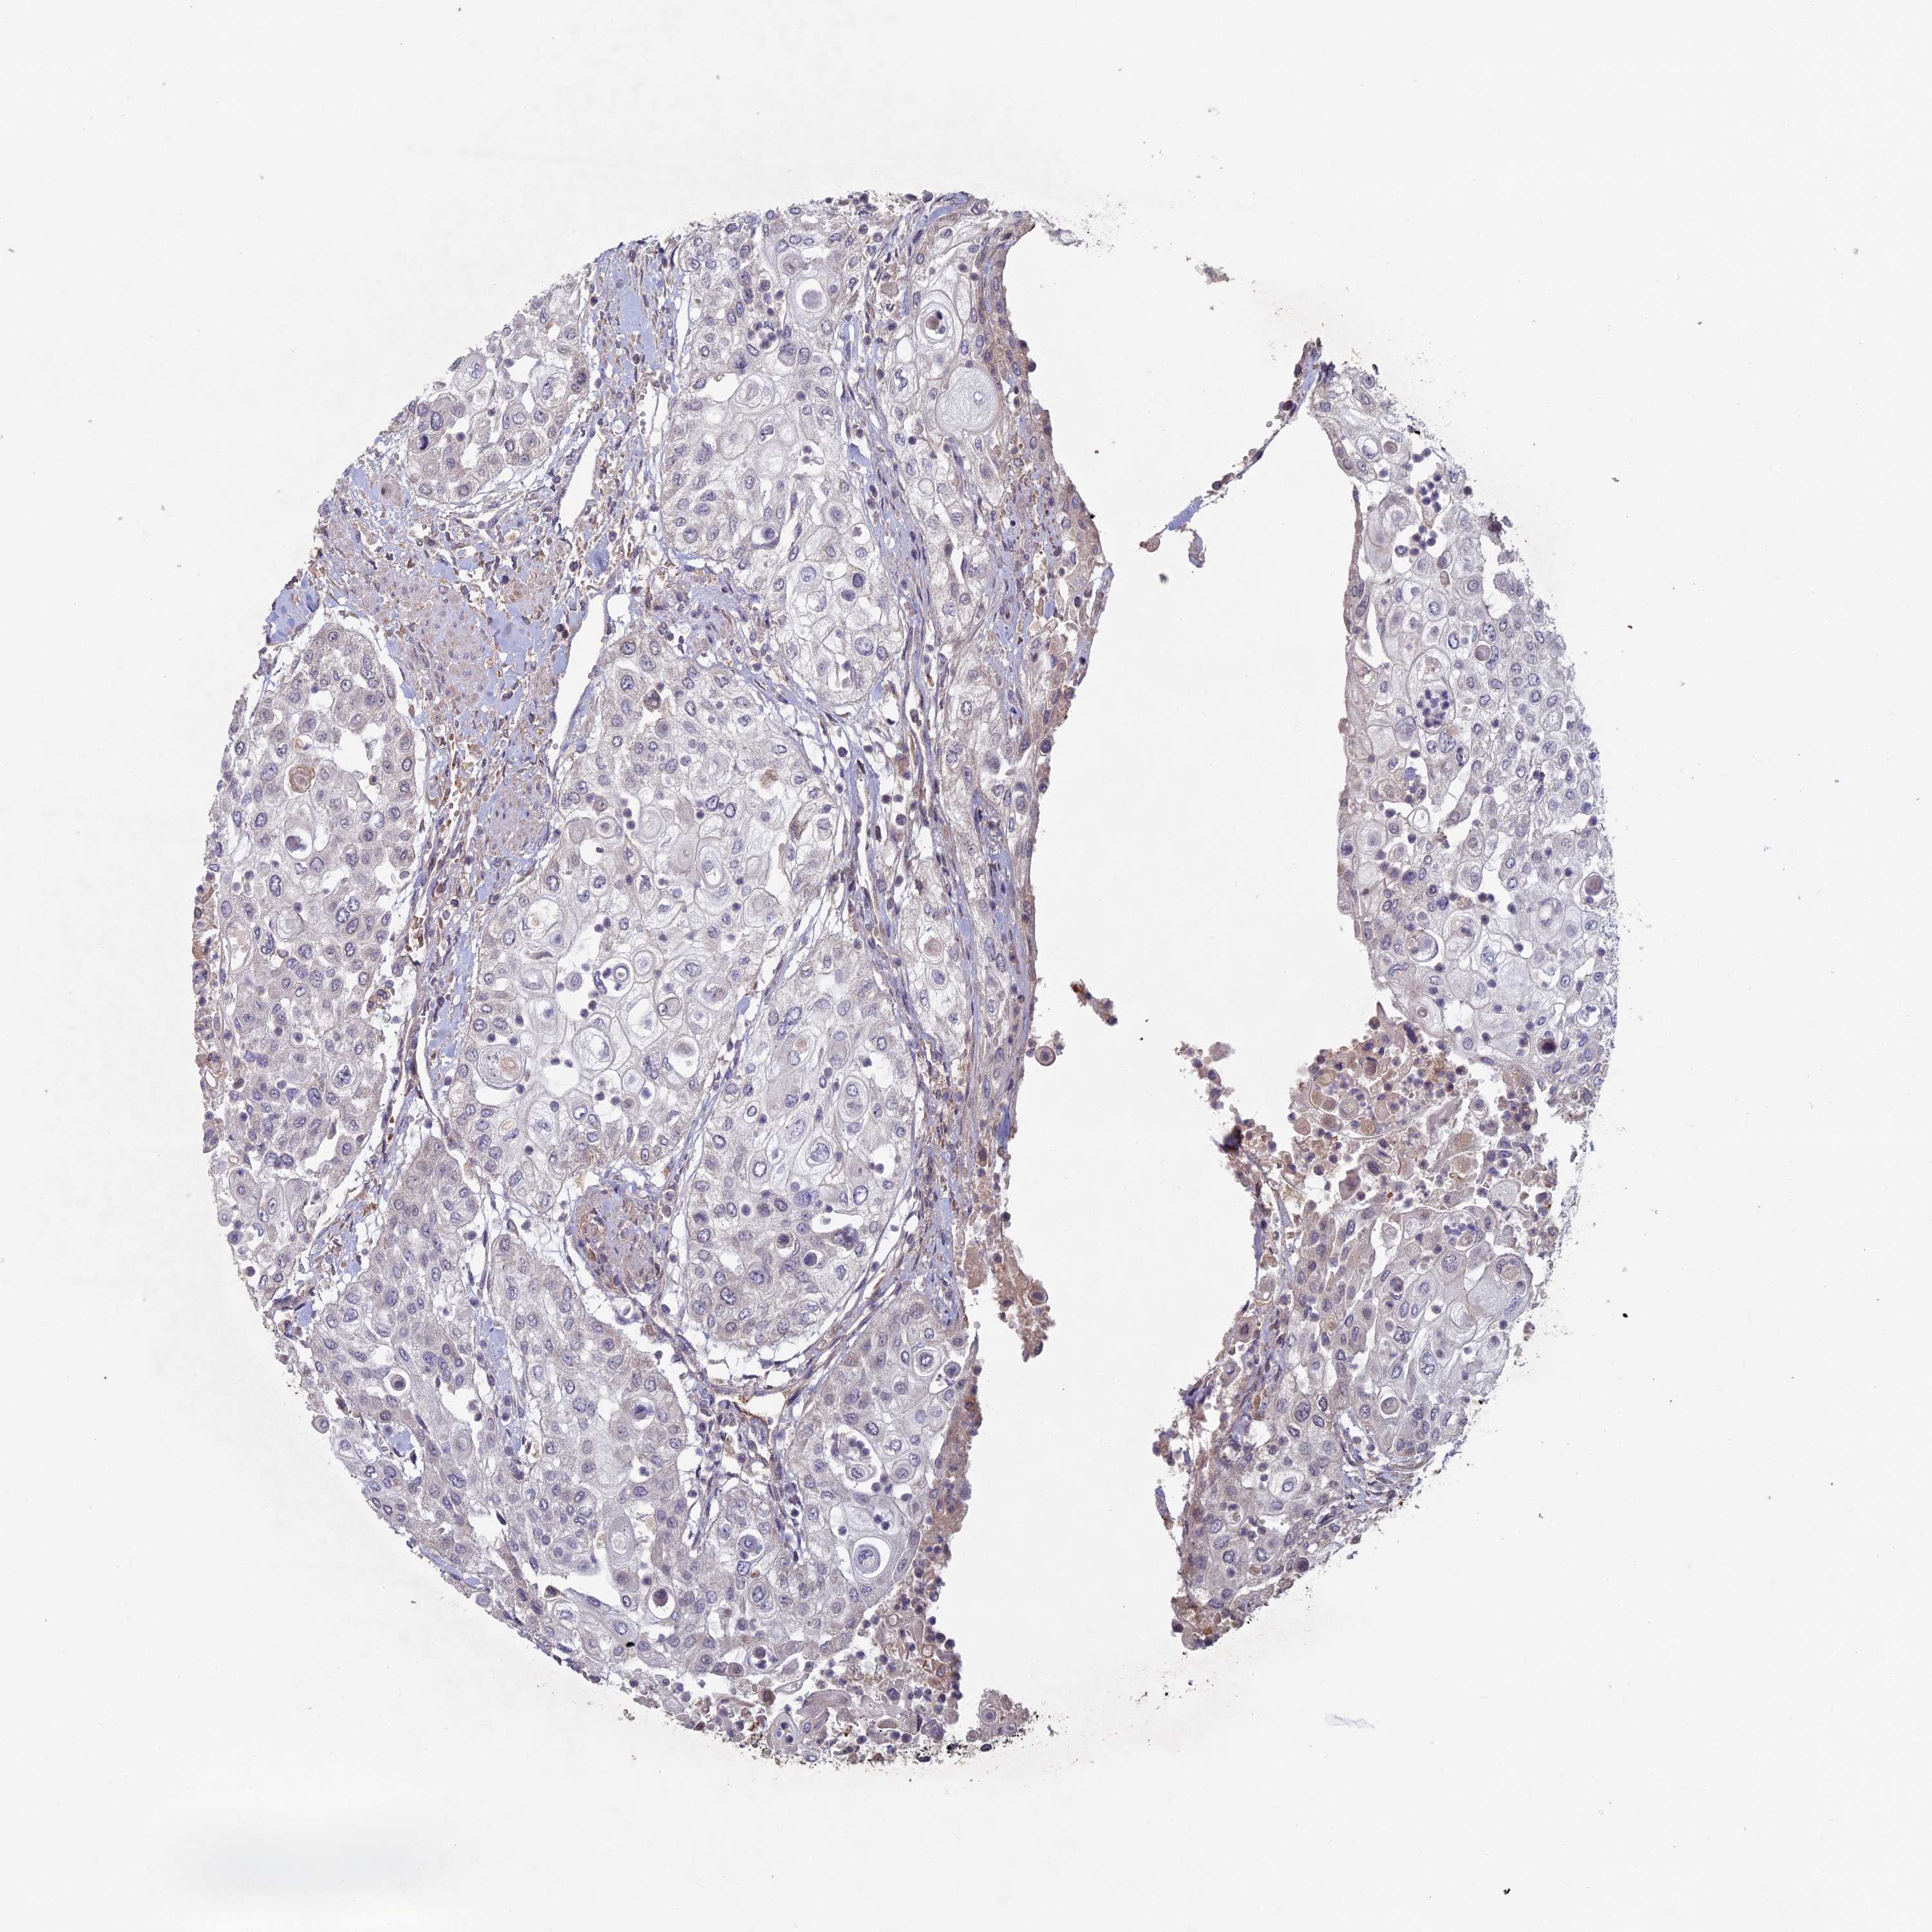

UROTHELIAL CANCER - Protein expressioni

A mouse-over function shows sample information and annotation data. Click on an image to view it in a full screen mode. Samples can be filtered based on level of antibody staining by selecting one or several of the following categories: high, medium, low and not detected. The assay and annotation is described here.

Note that samples used for immunohistochemistry by the Human Protein Atlas do not correspond to samples in the TCGA dataset.

Antibody stainingi

Antibody staining in the annotated cell types in the current human tissue is reported as not detected, low, medium, or high, based on conventional immunohistochemistry profiling in selected tissues. This score is based on the combination of the staining intensity and fraction of stained cells.

Each image is clickable and will lead to virtual microscopy that enables deeper exploration of all samples and also displays staining intensity scores, fraction scores and subcellular localization as well as patient and tissue information for each sample.

Antibody HPA039683

Antibody HPA040776

Staining

High

Medium

Low

Not detected

Intensity

Strong

Moderate

Weak

Negative

Quantity

>75%

75%-25%

<25%

None

Location

Nuclear

Cytoplasmic/membranous

Cytoplasmic/membranous,nuclear

Urothelial carcinoma, Low grade